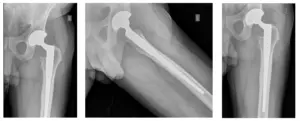

El paciente había hecho un seguimiento para revisar las radiografías. El paciente evoluciona favorablemente y se le realizará un seguimiento dentro de un año para controlar su ATC izquierda. El paciente está bien y no tiene dolor.

Radiografías de la THA izquierda. Las radiografías revelan que no hay fracturas y que la THA izquierda está bien alineada.